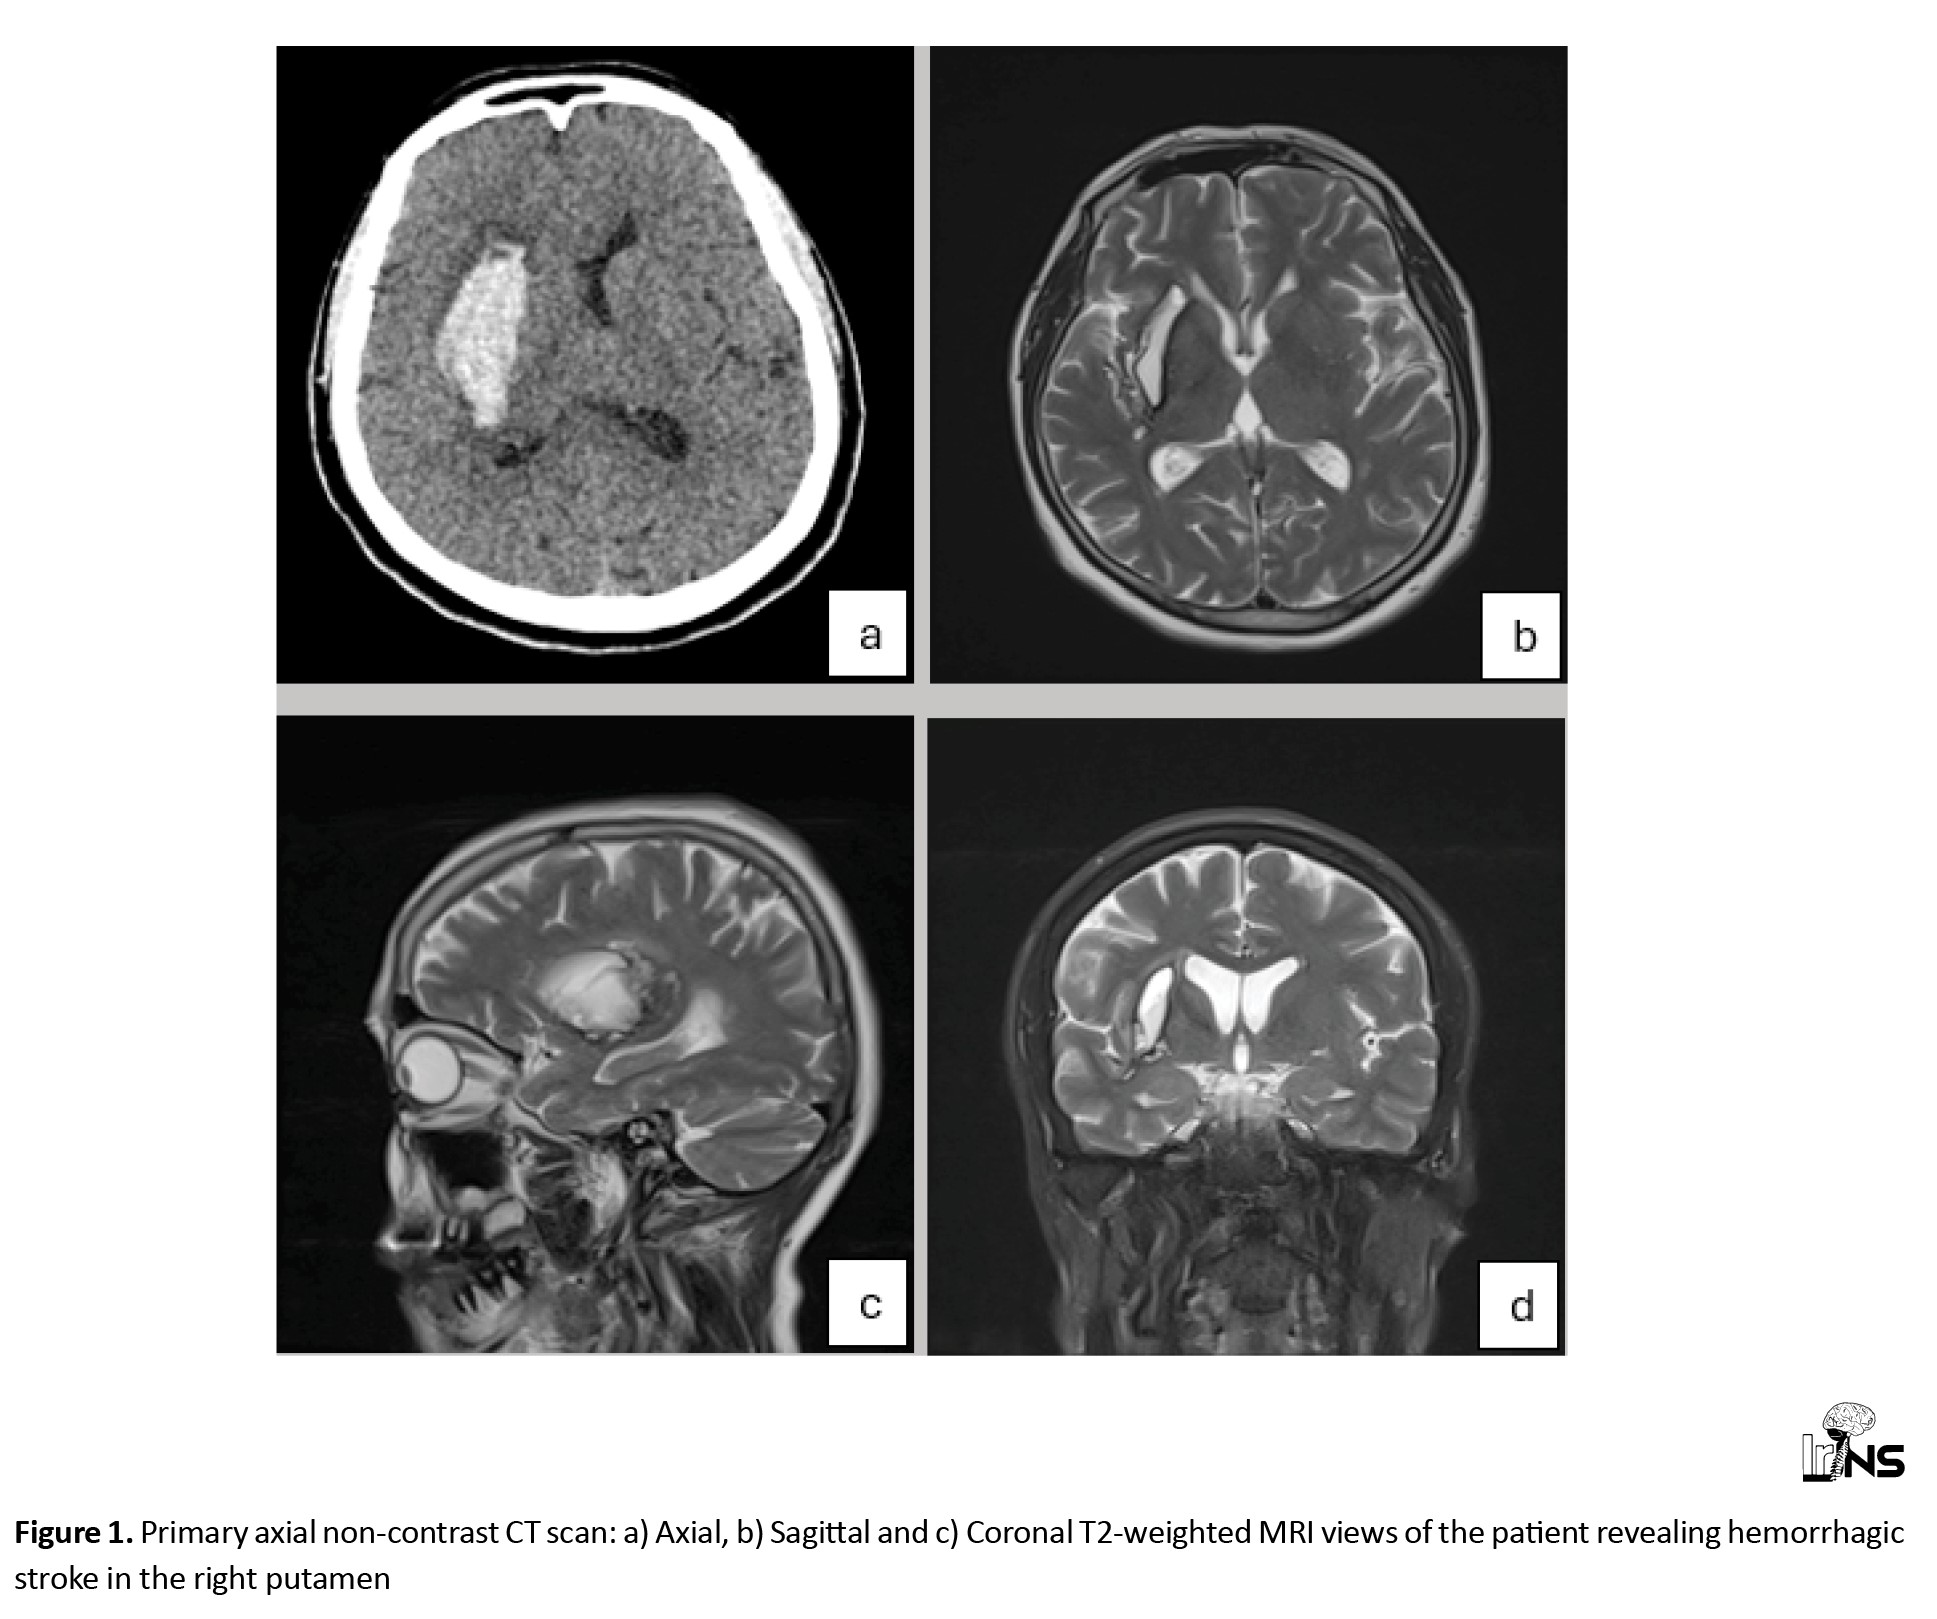

Herein, we present the case of a 58-year-old woman who was transferred to our hospital with headache, drowsiness and left hemiparesis. The patient had upper extremity force of 2/5 and lower extremity force of 3/5. The patient underwent a primary work-up using a non-contrast CT scan and magnetic resonance imaging (MRI) and was diagnosed with a suspected stroke. Imaging revealed a typical hypertension-related ICH in the right putamen (Figure 1).